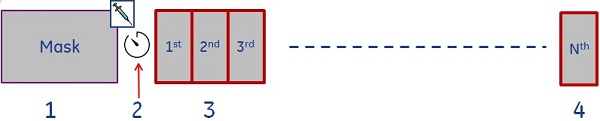

The visual display illustrates the acquisition time line. The time line diagram does not include the mask phase. - When the Total Phases value is greater than the Wash-in Phases value, the following scenario occurs.

Figure 5. Phases acquired when the Total Phases value is greater than the Wash-in Phases value. Note that every box represents a phase

Table 3. Image legend Number Description 1

Mask phase that occurs when the Mask Phase option box is selected. 2

Time of injection and initial delay that you enter for a pause between injection and start of the first phase. 3, 4

Phase 1 and phase 2---> W, where "W" represents the number of Wash-in Phases. 5 Delay after the last wash-in phase. 6, 7

Phase W +1 ---> Phase N, where "N" represents the number of Total Phases. - When the Total Phases value is the same as the Wash-in Phases value, the following scenario occurs.